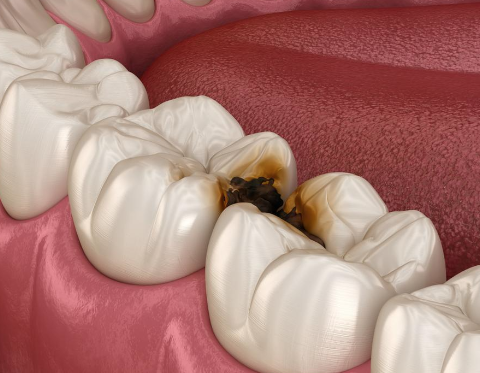

文章指出龋齿危害不容小觑,不仅影响口腔健康,还威胁全身健康。它会渐进破坏牙齿结构,从浅龋发展到深龋,导致牙齿敏感、疼痛,影响睡眠。还会降低生活质量,造成口臭,影响社交。此外,口腔细菌可能引发心血管疾病、影响消化,儿童龋齿还会影响恒牙发育。因此要重视预防和治疗,保持口腔卫生。